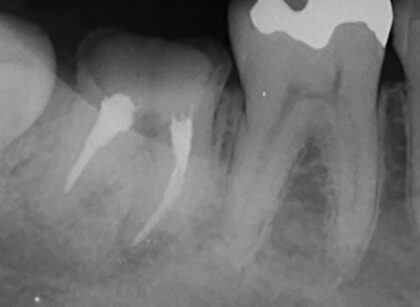

より細い器具を駆使して対応し、無事根の先の病巣までアプローチをすることができました。

奥のほうから汚染された組織が見つかり、可能な限り除去したので改善がみられることを期待してます。

術後は仮歯で様子見ながら本歯に置き換えていきます。